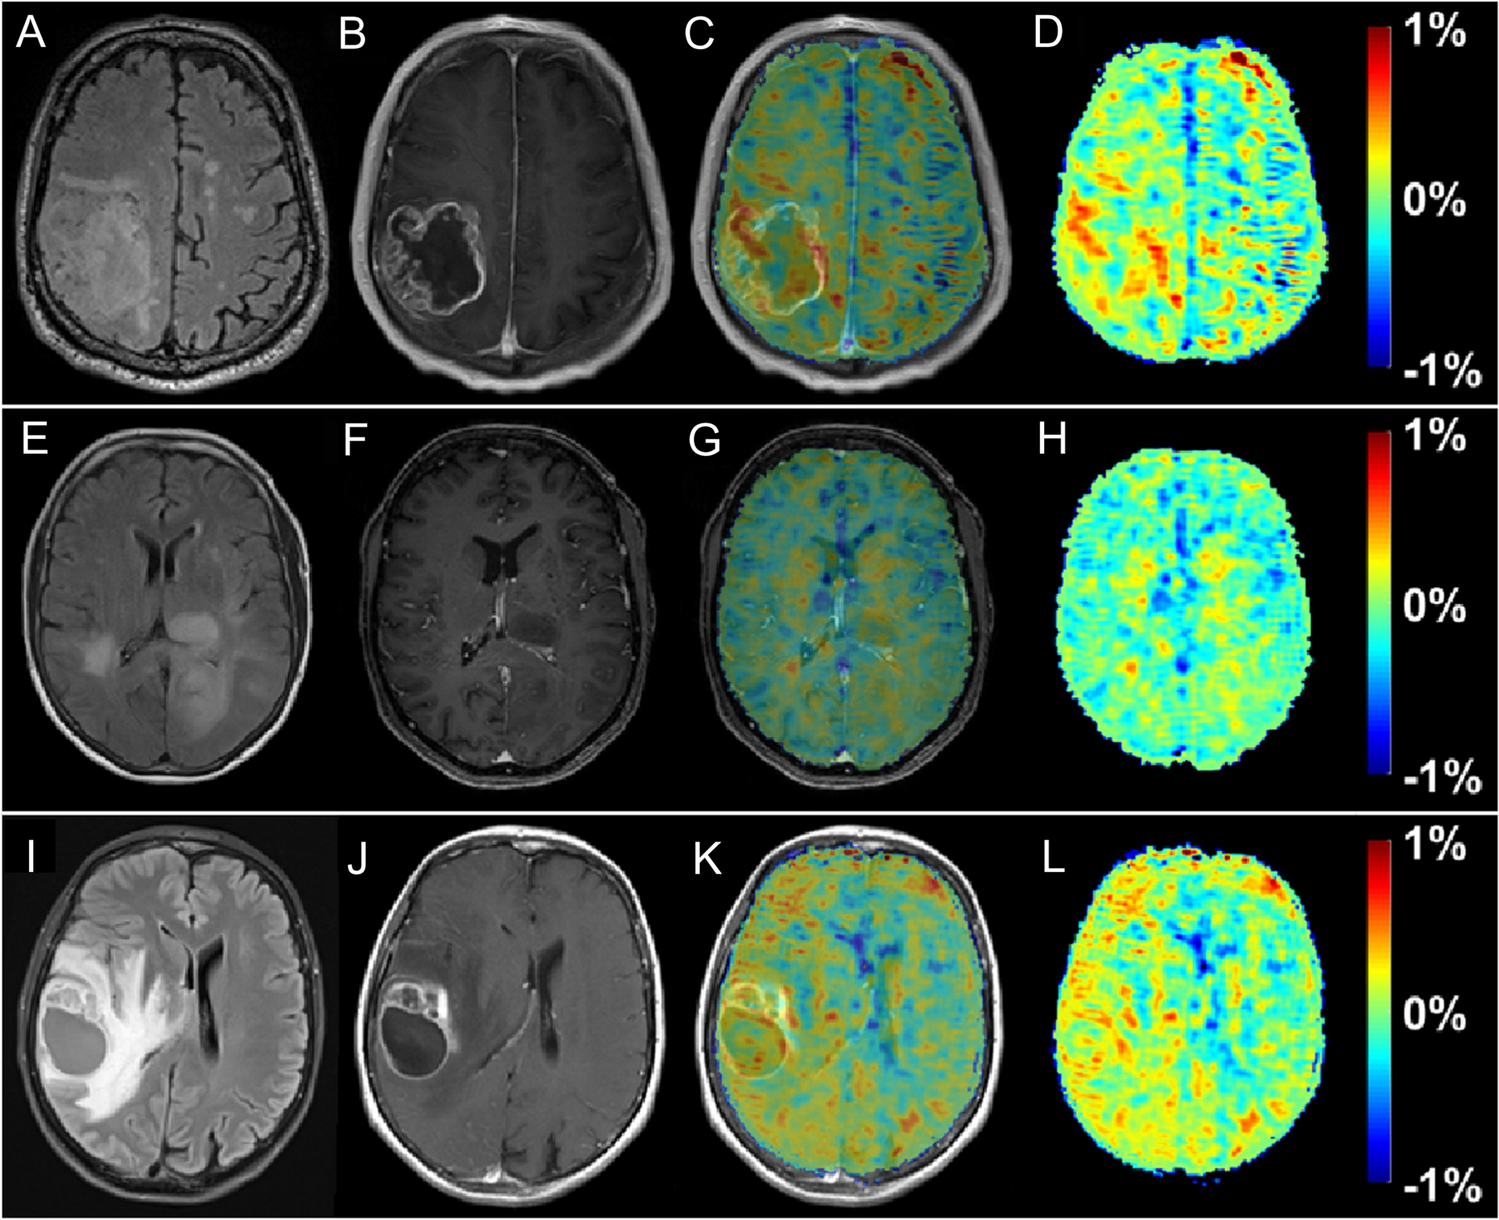

DGE and DGEρ imaging in brain

Contrary to body applications, early experience shows that DGE and DGEρ signal detection in human brain seem possible at 3 T [22, 23] if appropriate post-processing steps, i.e., corrections for motion-related artifacts are applied. Although the effect size was small, generated DGEρ maps showed unique patterns, partially correlated with the gadolinium (Gd)-based T1 tumor ring enhancement. In a study of 3 glioma patients, a significant glucose uptake could be observed with a DGEρ effect strength in the range of 0.5% of the water signal for the patients with BBB breakdown. Statistical evidence can decrease when uncorrected motion is included as a thorough analysis revealed.

Compared to reported effects at 7 T in humans of 2–6% [17, 19], the observed DGE effect size of ~ 0.5% at a clinical field strength of 3 T is small, but consistent with Bloch simulations, where the effect was calculated to be two to three times smaller than at 7 T. The maximum effect size was observed approximately 8 to 9 min after beginning of glucose injection in general, which is in good agreement with the literature on animal experiments [69]. The different contributions to the signal, especially vascular and intracellular contributions are still discussed in the literature. On the contrary, there is a consent in the community that glucose leaking through a damaged BBB into the extravascular, extracellular space contributes to a large extent to the glucoCEST signal. Therefore, a correlation between Gd contrast-enhanced images and DGE images is expected as Gd-based agents would also enter this space via a BBB breakdown. The following observations were made further [70]: first, when a visible strong or faint BBB breakdown can be observed, in general a positive DGE signal was also detected. However, spatially, there was only a rough match with the tumor region indicated by the Gd enhancement, i.e., between the hyper-intensity patterns in the DGE and the DCE contrast. The observed hyper-intense areas in the DGE maps might originate primarily from higher glucose levels or lower pH values attributed to higher tumor activity. However, it is impossible to define at this stage what the main source of signal enhancement is. Such a conclusion requires a larger dataset if possible with a higher signal to noise ratio and higher contrast to noise ratio for DGE. At the moment, the relation between DCE and DGE cannot be fully described and one cannot rule out that some of the differences are due to the lower sensitivity of DGE compared to DCE (Fig. 12).

Fig. 12

T2 FLAIR (A, E, I), T1‐ce (B,F,J), T1‐ce with overlaid ∆DGEρ map (C, G, K), and the ∆DGEρ‐maps (D,H,L) of patient 1 (AD, ~ 7 min post-injection), 2 (EH, ~ 7 min post-injection), and 3 (IL, ~ 9 min post-injection). From [22], with permission